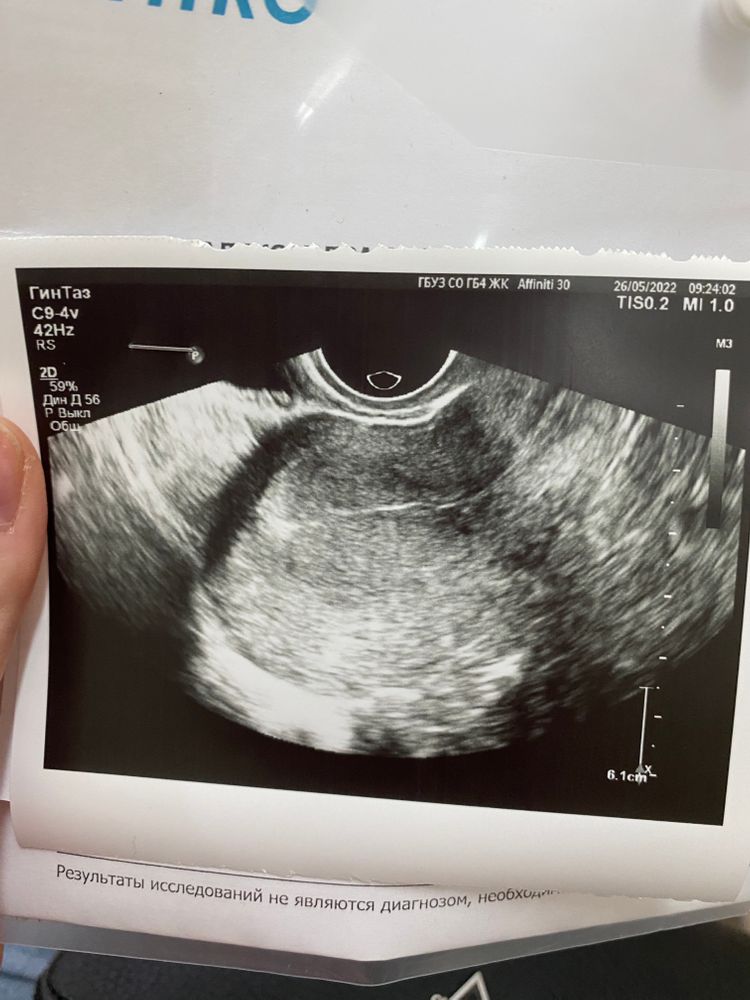

Есть или нет?

Ну, скажем так, любую точку можно принять за ПЯ, я таких тут три вижу, но узист бы точно определил ПЯ, если б видел. Видят от 3-4 мм, ну 4 мм точно, т.е.2 недели от зачатия.

На снимке нет ничего.Какой у вас хгч?

Что написано в заключении?по фото узи-плодного яйца нет.может вам для начала сдать хгч?

Я не вижу. Но Вы и, правда, очень рано пошли. Переделайте через неделю. Вдруг))

Нет ничего. Плодное яйцо выглядит вот так Изображение Черное пятнышко.

Вы действительно рано пошли. Показали бы нам что написано в заключении, мы глянули бы размеры эндометрия, жт.. и можно было хоть сказать это похоже не беременность или нет. Но эндометрий такой у вас.. секреторный, рыхлый весь, судя по картинке.

Shura , да, точно беременны. Эндик 21 мм) вам надо ещё неделю вытерпеть и найдут пя)

На УЗИ ничего нет, срок очень маленький